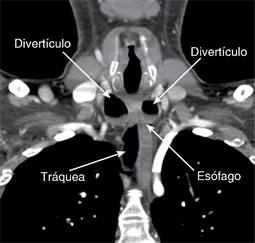

Figura 2: Tomografía a nivel cervicotorácico en corte coronal, que muestra localización de divertículos esofágicos de Killian-Jamieson.